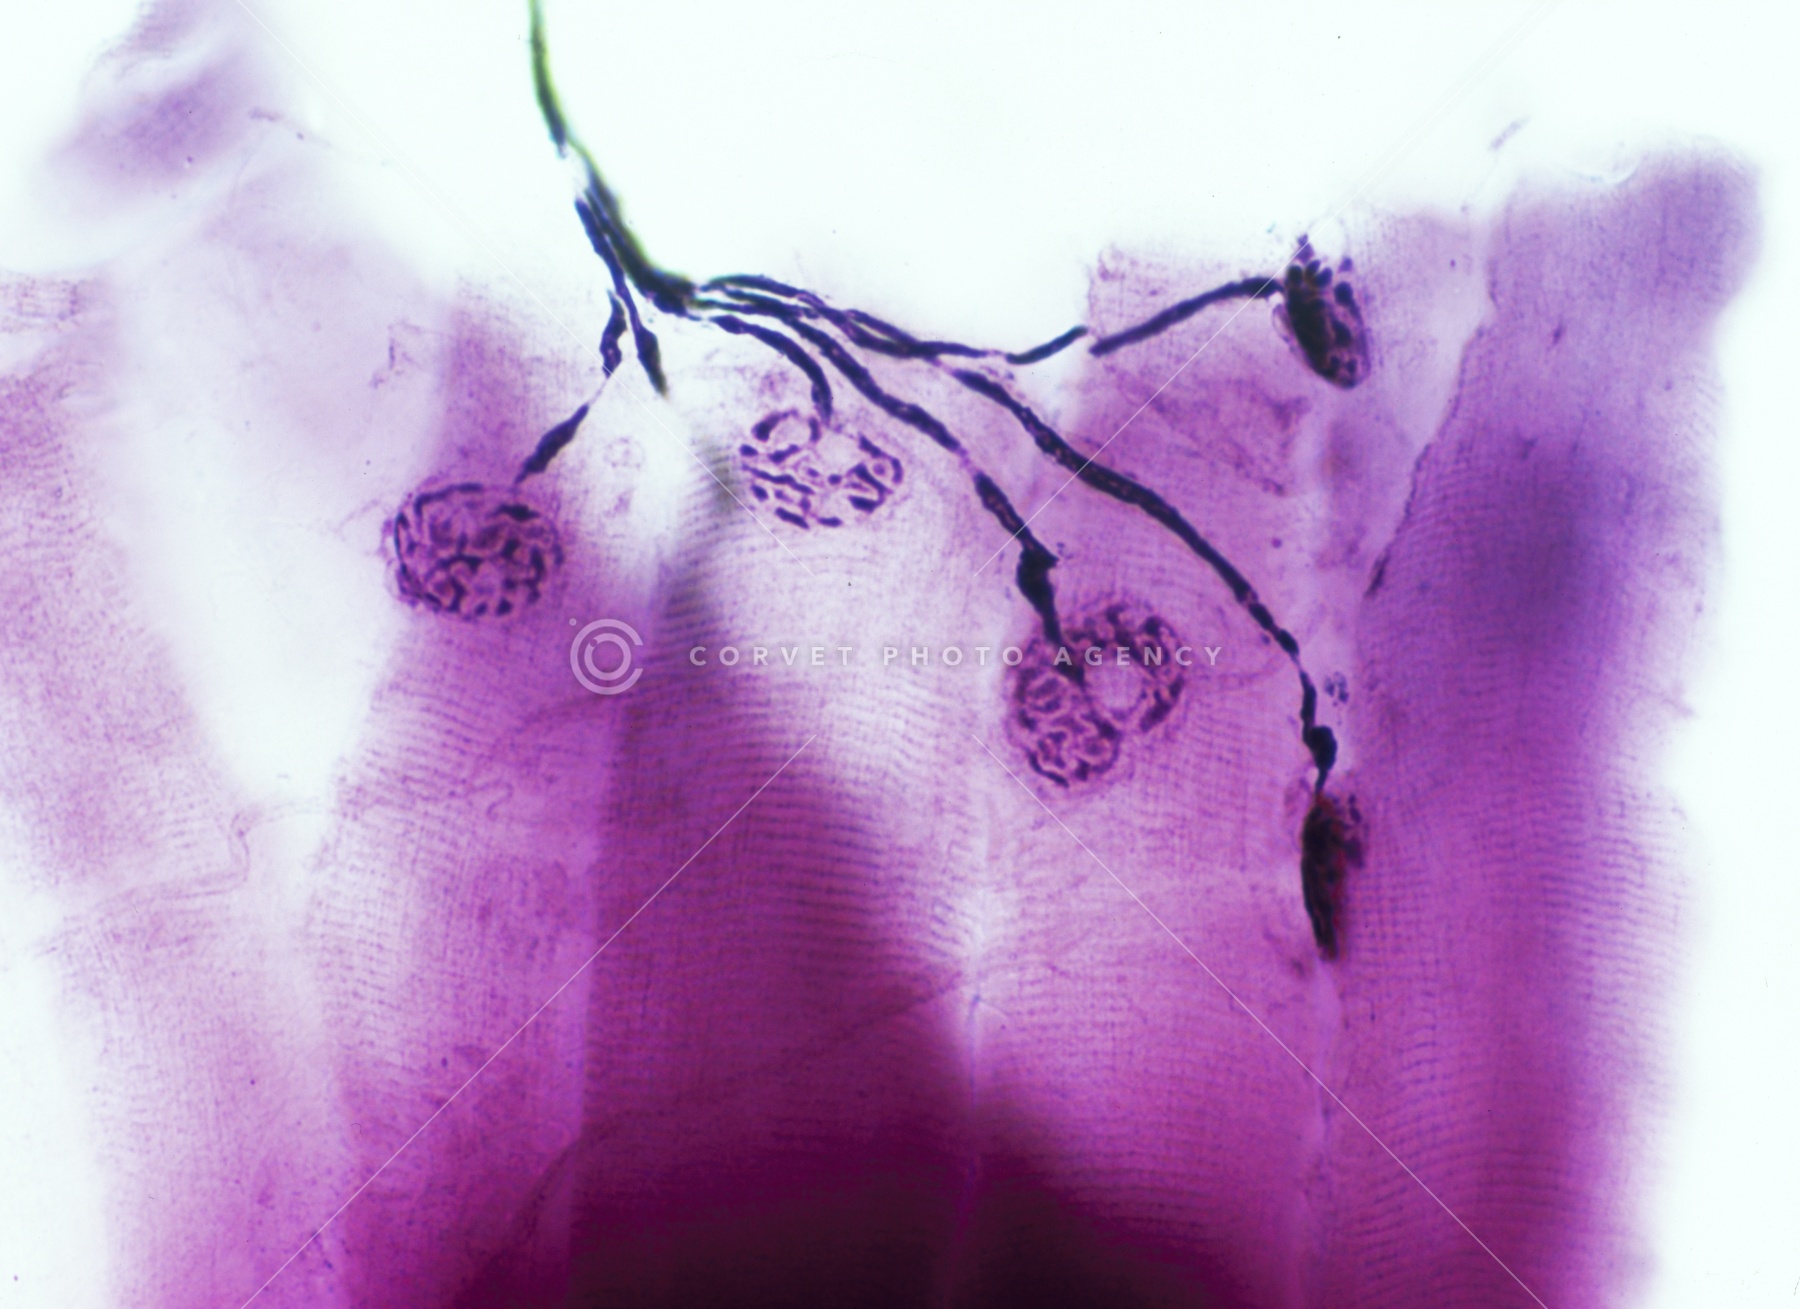

運動神経終板 ヘビ

運動神経終板(ヘビ) 染色 顕微鏡倍率200

運動神経終板 ヘビ

運動神経終板(ヘビ) 染色 顕微鏡倍率200